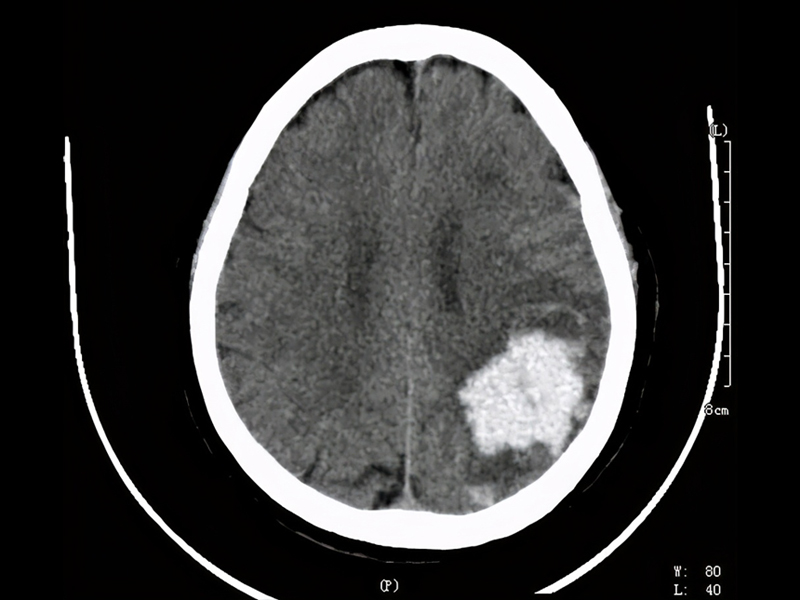

據報道,這名程序員吳先生從事技術工作,月薪高達 3 萬元人民幣,但每天的工作時間從早上 7 點持續到凌晨 1 至 2 點,長期處於極度疲勞狀態。今年年初,他因腦幹出血 5 毫升陷入昏迷,昏迷長達 15 天,在 ICU 搶救 28 天後才逐漸恢復意識。隨後,他又轉入康復醫院進行 70 多天的治療,目前已恢復約 70% 的身體功能,但仍無法完全康復。

吳先生在接受媒體採訪時表示,生病後家庭經濟壓力陡增,治療費用高達 50 萬元人民幣,且失去了穩定收入來源。他坦言,自己曾為了追求高薪而壓抑自我需求,如今才明白健康的重要性。他在社交媒體上分享了自己的康復日記《腦幹出血 ICU 昏迷後 60 天康復重獲行走》,並呼籲網友珍惜身體,「如果能見到以前的自己,我想對他說:好好愛自己。」

吳先生還特別提醒大眾,若經常熬夜且出現手指手掌麻木的情況,應立即就醫。「三天是黃金時間,否則可能導致腦溢血、半身不遂,甚至無法手術治療,只能靠養護慢慢恢復。」